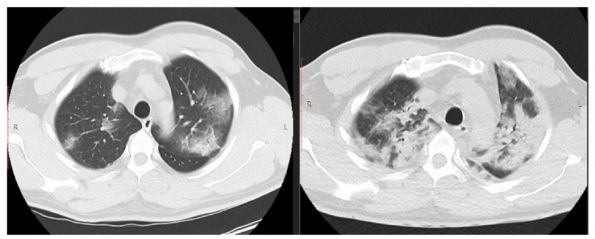

Участки по типу консолидации